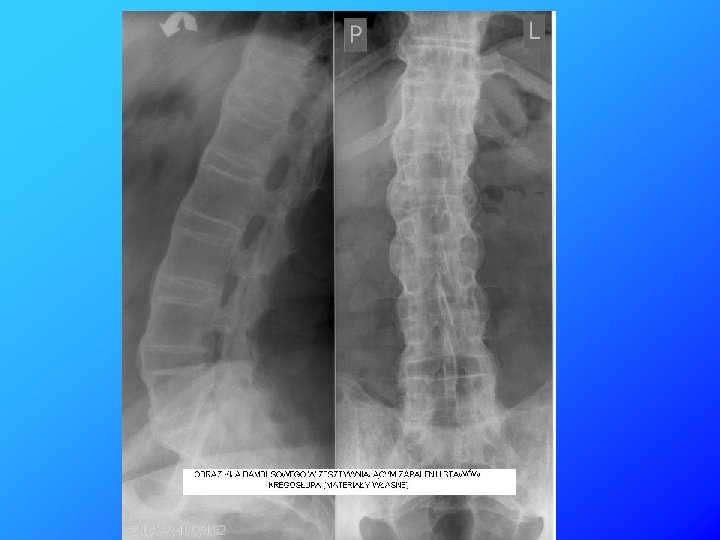

U pacjenta rozpoznano zesztywniające zapalenie stawów kręgosłupa (ZZSK), które powoduje zarastanie przestrzeni międzykręgowych. Zmiany ograniczają ruchomość kręgosłupa dając na zdjęciach RTG charakterystyczny obraz „kija bambusowego”.